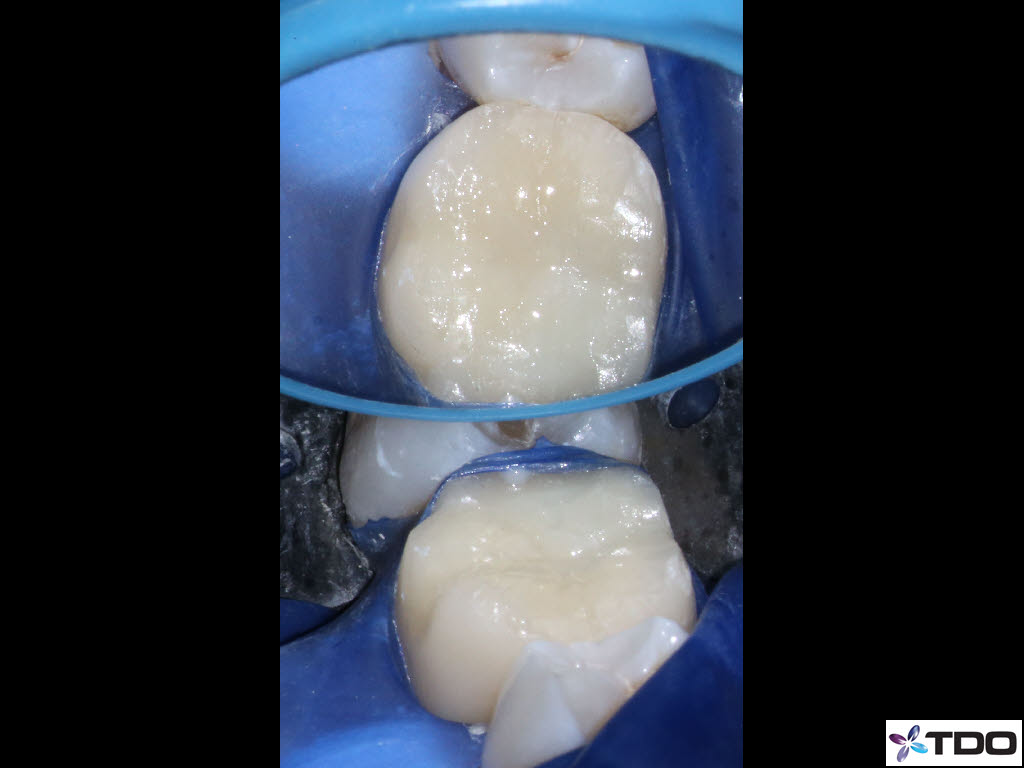

In the hierarchy of dentin conservation the existing restorative has the lowest priority and it quite frankly gets in the way of our access to the root canal system. But, after practicing directed dentin conservation for a while, you sometimes get lucky. The patient is 40yo. She was symptomatic at the time of treatment and interestingly the mesiobuccal canal was partially vital while the mesiolingual, distobuccal and distolingual canals were partially necrotic. She was asymptomatic at the completion visit as well as at the follow-up appointments.

Hi Gergely. The crown was less than two weeks old when the patient was first seen in my office. The previous crown was 15 yrs old and was seldom sensitive; the RD replaced the crown due to an “open margin.” Heat/cold sensitivity ensued after the crown prep. Four days after the permanent crown was cemented the patient woke up with severe throbbing pain and the temp sensitivity became worse. When she presented to my office she reported severe biting tenderness and tender submandibular lymph nodes.